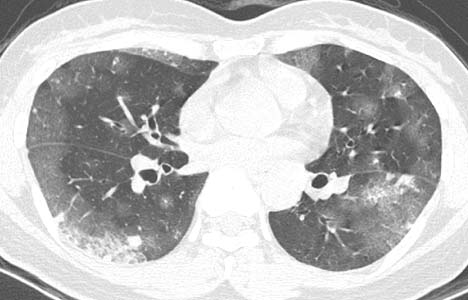

患者女性,43岁,肝癌tace治疗后出现胸闷不适.

请分析肺部改变的成因及可能的诊断.

动静脉瘘,栓塞剂经瘘口进入肝静脉--下腔静脉--右心房--右心室--肺动脉--沉积于肺内.

原发性肝癌进行栓塞治疗时,若肝动脉造影显示肿瘤侵犯肝静脉,且有明显的肝动静脉瘘,则使用碘油乳剂就不妥当,因为大量碘油可通过瘘道进入肺部,引起肺栓塞的并发症。

国内颜志平等报道:动物实验表明,碘化油进入肺部致死量约为0.5ml/ kg ,少量碘化油进入肺部可通过肺部吞噬细胞进行“消化”,故少量碘化油进入肺部后一般经过对症处理后,一般不会遗留明显并发症。